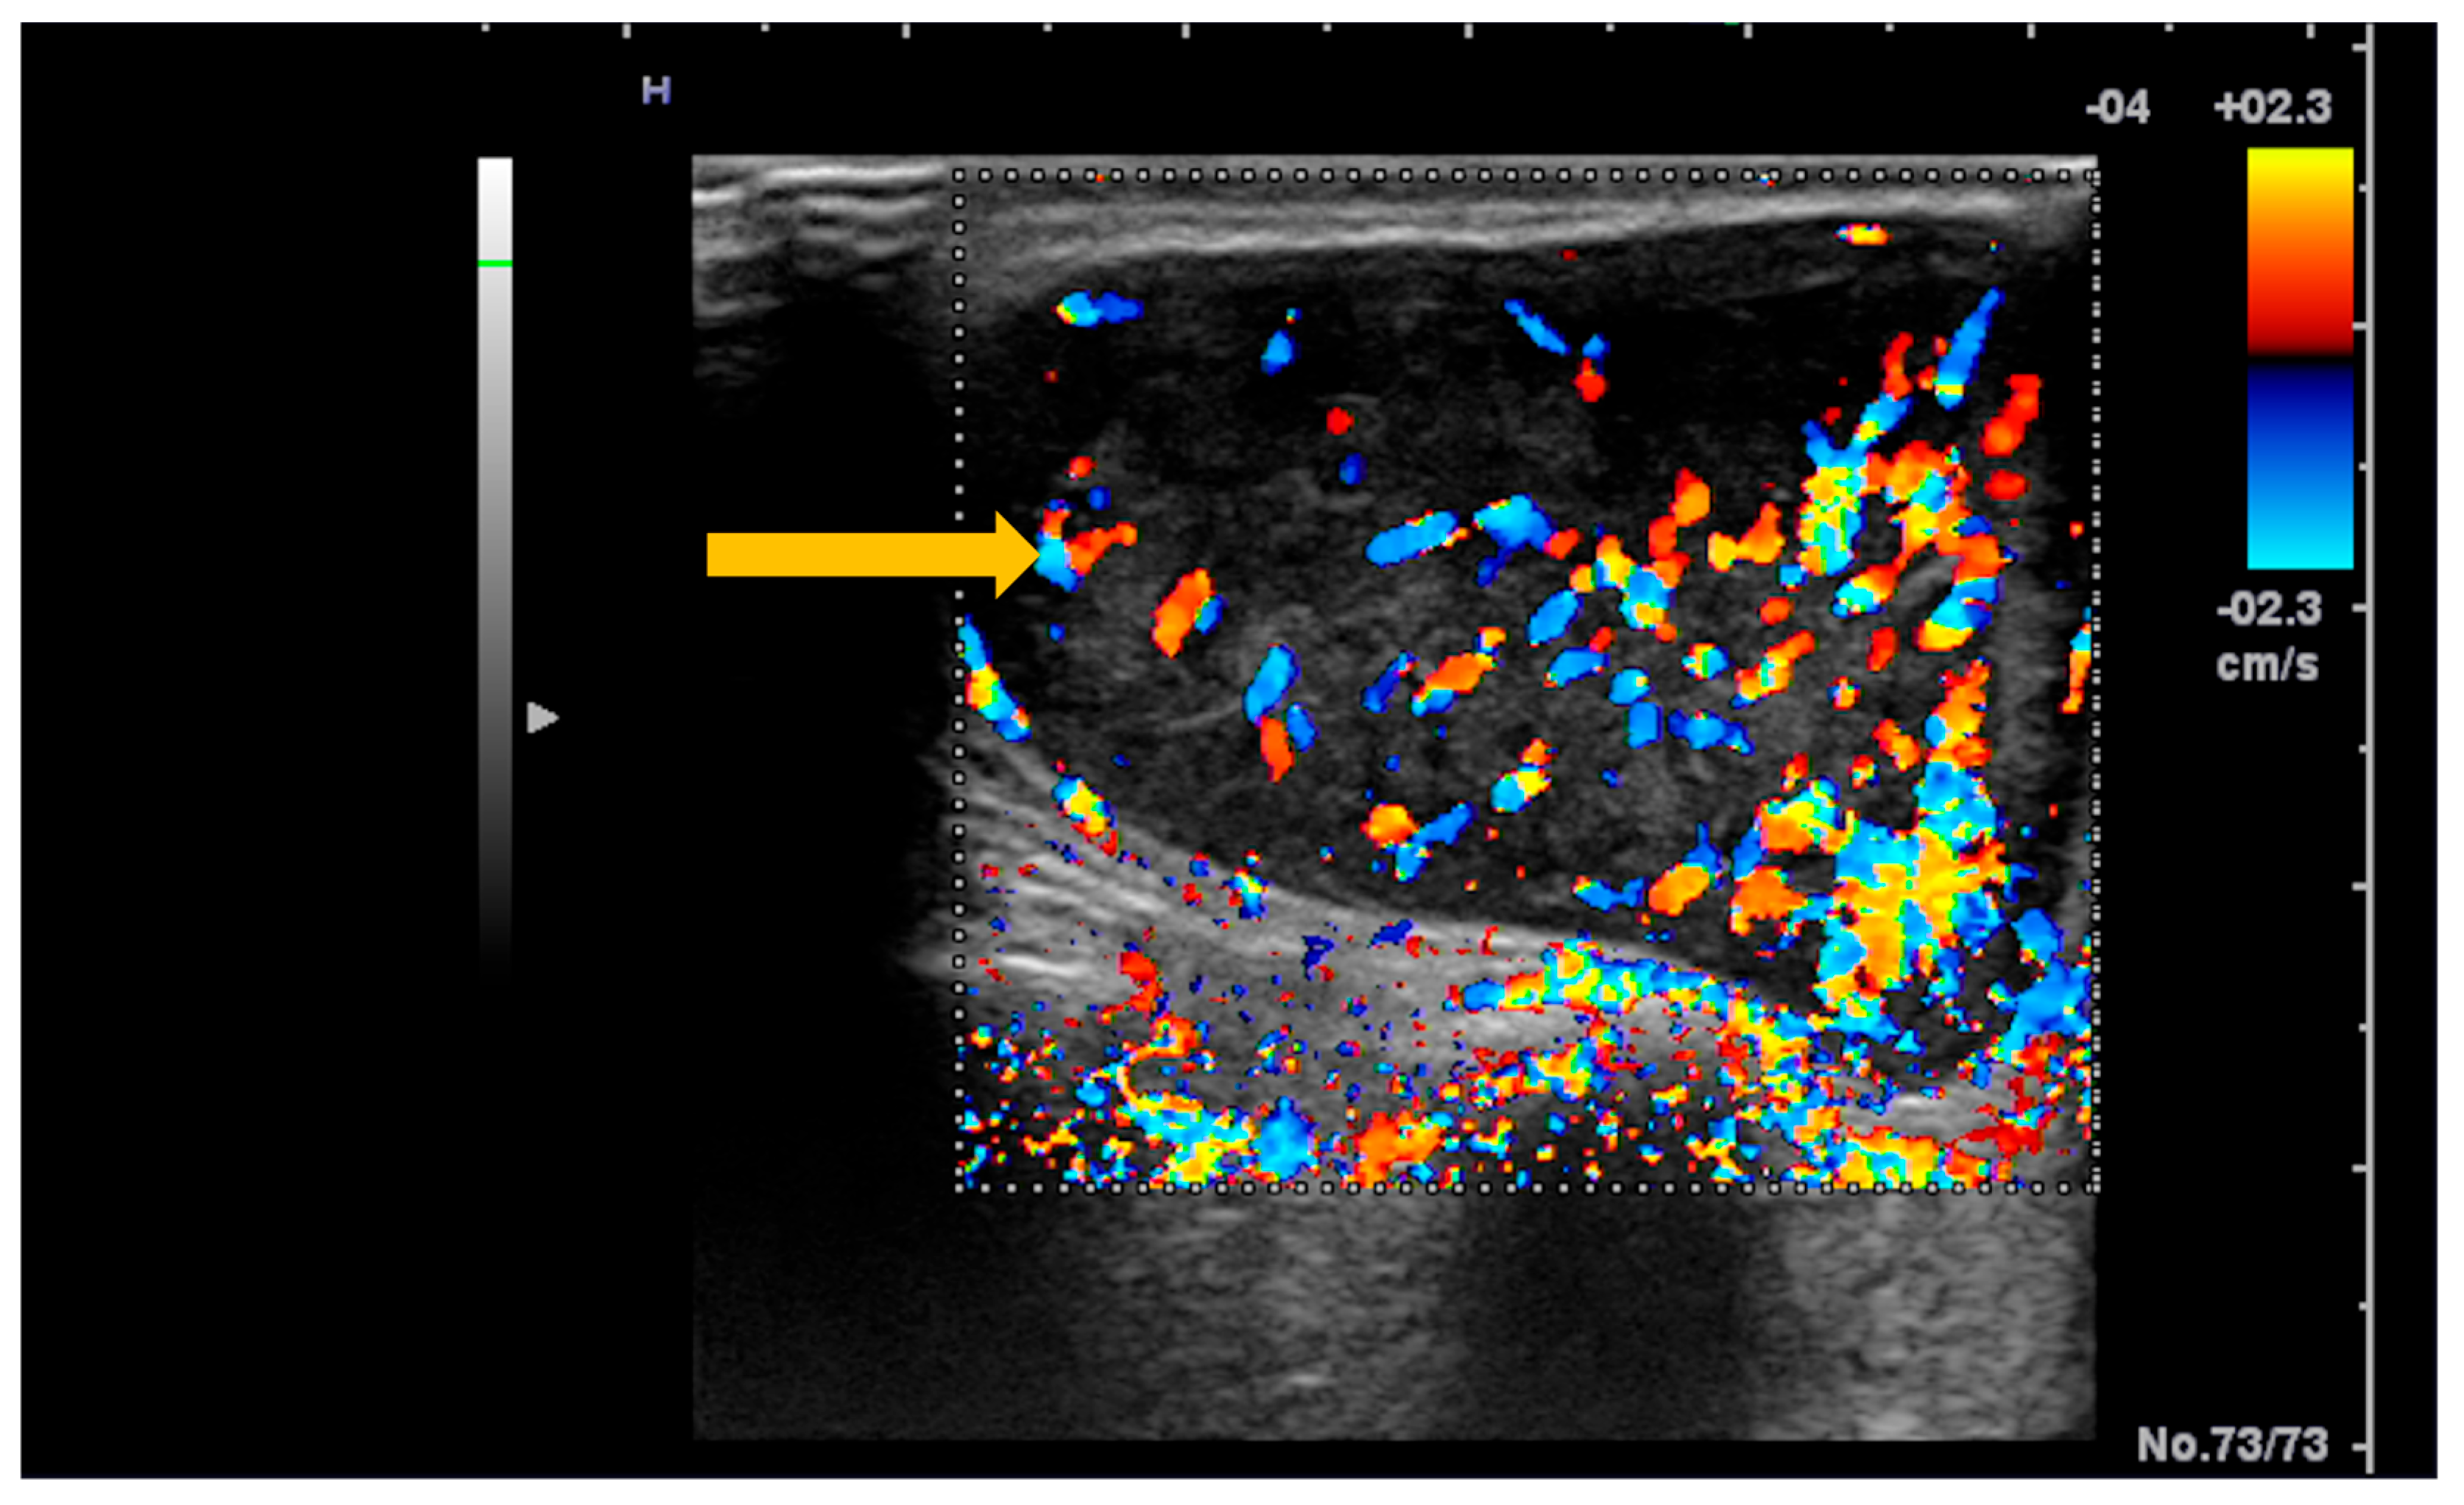

Ultrasonography is the imaging tool most frequently used in clinical practice due to its non-invasive nature, low cost, and wide availability [64]. Dynamic ultrasonographic evaluation of the salivary glands can identify a newly developed hypervascular, oval, relatively well-defined, hypoechoic nodular lesion with intrinsic hyperechoic septa and posterior acoustic enhancement (Figure 8 and Figure 9) [64,65]. At the same time, ultrasonography can be used to guide biopsies of lesions with suspicious imaging characteristics [63].

Figure 9. Color Doppler ultrasound of the parotid gland in a patient with Sjögren’s syndrome. Color Doppler imaging demonstrates a newly developed hypervascular nodular lesion within the parotid gland (arrow), a finding suspicious for salivary gland lymphoma in the clinical context of Sjögren’s syndrome.